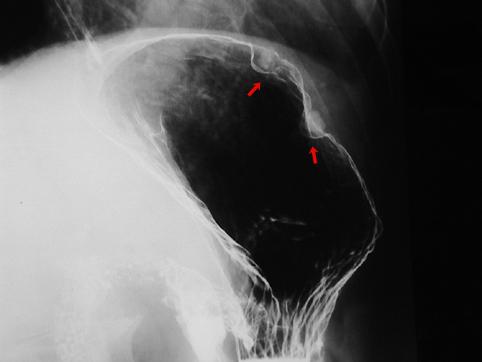

질환(병리주체)의 분류 종양양 병변/벽석탄화 병변

부위(장기별) 위(부위)/궁륭

검사방법 X-P

종양의 최대경(밀리미터) 1~9